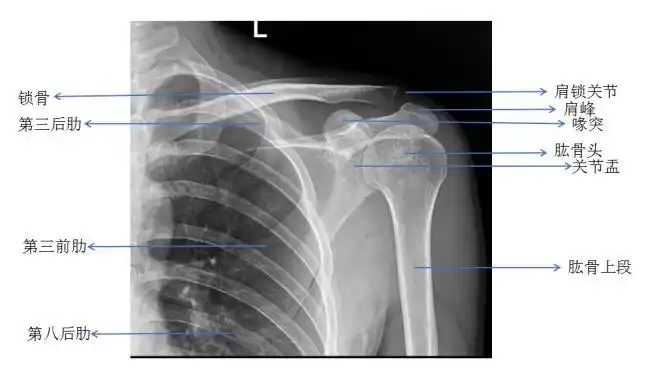

肩关节正常正位片